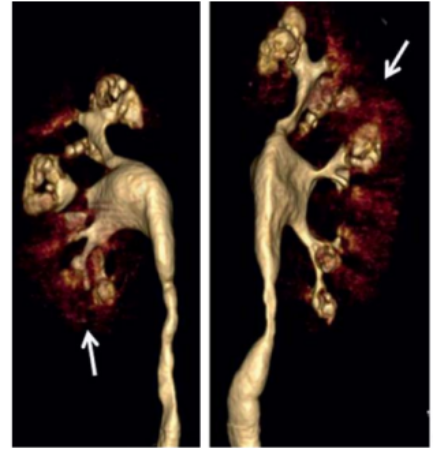

2.结晶成核。滞留的尿液让钙、磷、草酸等分小子浓度飙升,并逐渐达到过饱和状态,再加上其他相关促石因子的干预,矿物质们开始凝聚成微结晶,从而形成以草酸钙或磷酸钙为核心的结石。他们像葡萄串般填充在扩张的集合管里,CT扫描时会出现标志性的“花簇状”影像。

图5 MSK结石的增强CT三维重建,可见囊状扩张的集合管出现标志性的"花簇状"的景观。